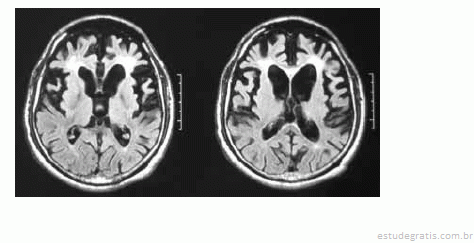

Uma mulher de 55 anos de idade, sem comorbidades, há três anos começou a apresentar distúrbio do comportamento, comprometimento do senso moral, da autocrítica, do poder de abstração e da memória. No exame, ela pouco colaborava com o examinador, possuía uma rigidez axial e apendicular, além de sutil tremor em repouso. O exame de imagem (RNM) a seguir foi realizado para auxiliar o diagnóstico.

Com base nesse quadro clínico, julgue os itens subsequentes.

A doença dos corpos de Lewy é o diagnóstico mais provável para essa paciente, tendo em vista a idade em que os sintomas se manifestaram, o seu quadro clínico e principalmente a RNM do crânio.Comentários